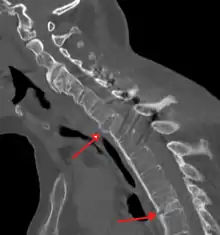

The earliest changes demonstrable by plain X-ray shows erosions and sclerosis in sacroiliac joints. Progression of the erosions leads to widening of the joint space and bony sclerosis. X-ray spine can reveal squaring of vertebrae with bony spur formation called syndesmophyte. This causes the bamboo spine appearance. A drawback of X-ray diagnosis is the signs and symptoms of AS have usually been established as long as 7–10 years prior to X-ray-evident changes occurring on a plain film X-ray, which means a delay of as long as 10 years before adequate therapies can be introduced.[24]

CT scan showing bamboo spine in ankylosing spondylitis